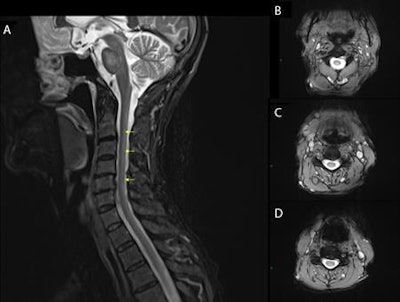

The 62-year-old man had been referred to a neurology clinic after developing numbness, pain, and weakness in his legs. The symptoms had lasted for more than six months, according to the authors from Queen Elizabeth University Hospital in Glasgow, Scotland. MRI revealed spinal cord abnormalities, and the patient was diagnosed with the rare neurological disorder after several tests.